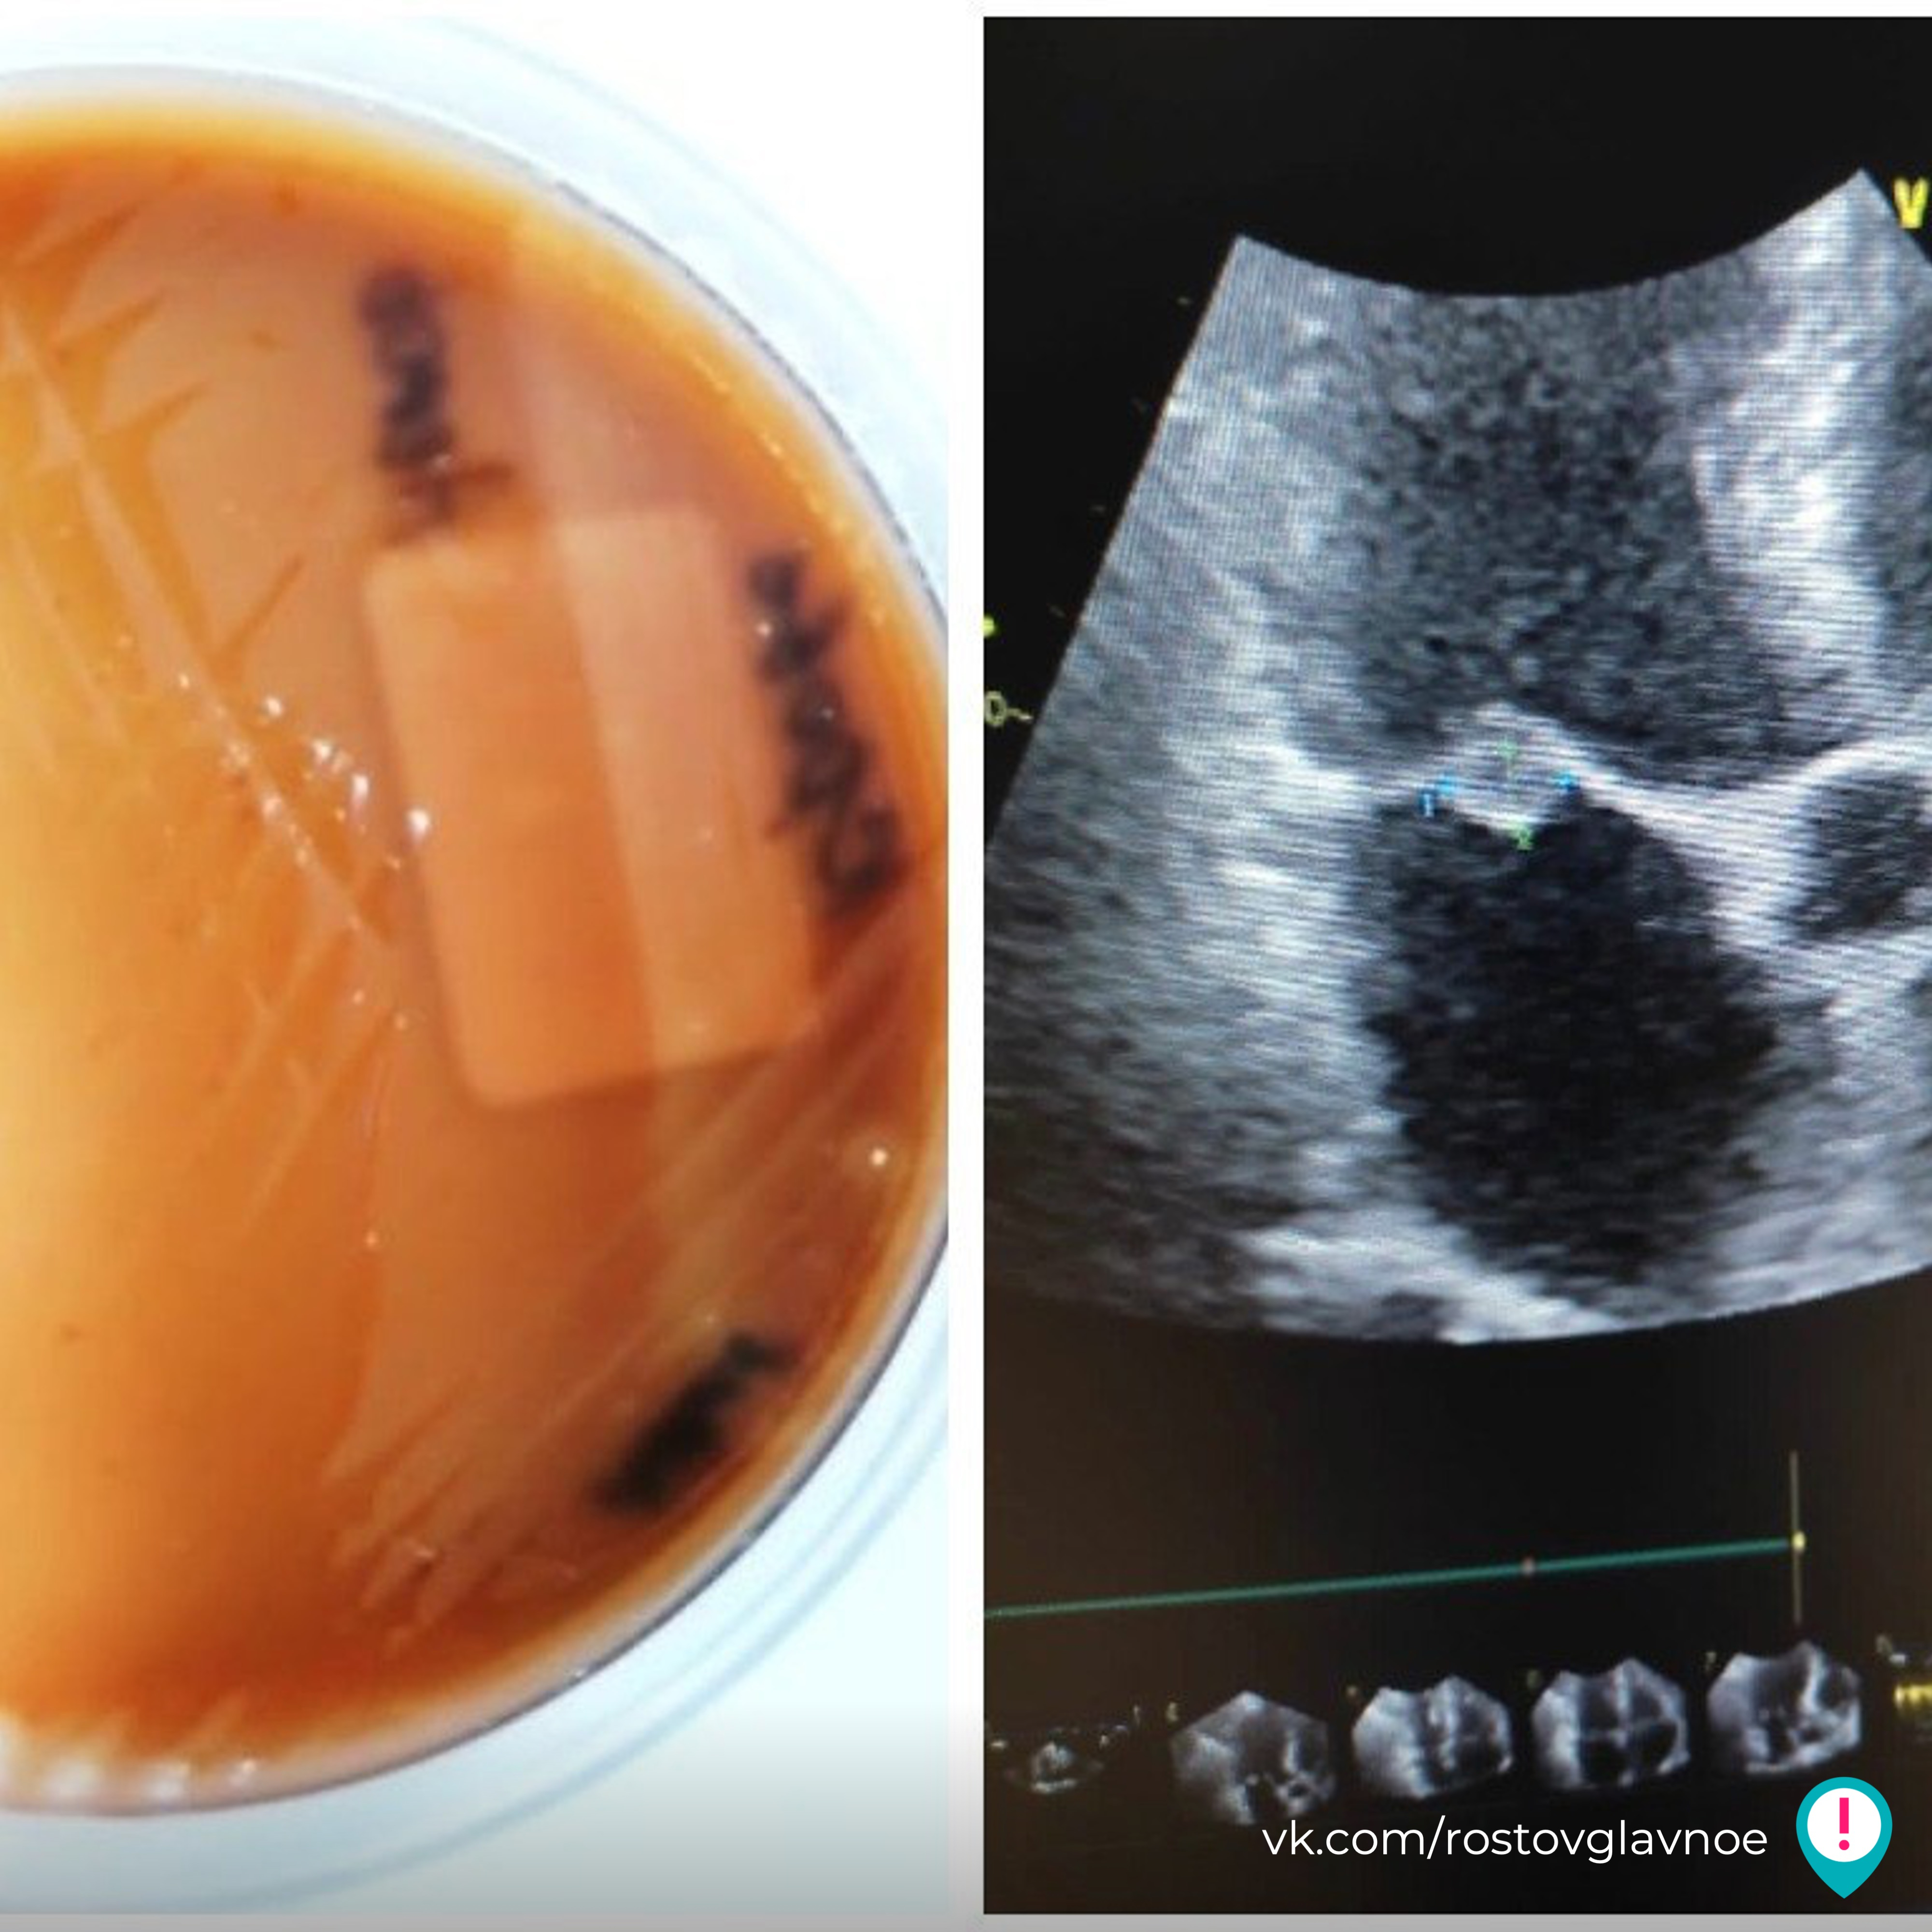

В Ростове операция по удалению зуба обернулась для мужчины серьезными последствиями.